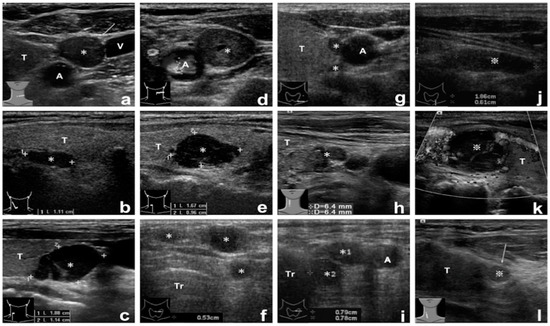

2. Materials and Methods

2.2. Tissue Aspirate PTH Assay